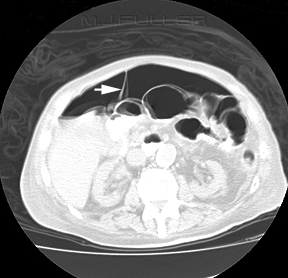

VIVA SCENE: CT ABDOMEN SHOWING FREE AIR

- The diagnosis of GI tract perforation is based on the direct CT findings, such as discontinuity of the bowel wall and the presence of extraluminal air, and on the indirect CT findings, such as bowel wall thickening, abnormal bowel wall enhancement, abscess and an inflammatory mass adjacent to the bowel

- The air may not be contained within any visible bowel wall.

- Direct visualization of the discontinuity of the bowel wall can specify the presence and site of GI tract perforation, which is marked by a low-attenuating cleft that usually runs perpendicular to the bowel wall on CT

- The falciform ligament may become outlined with air in a supine patient with free abdominal gas.